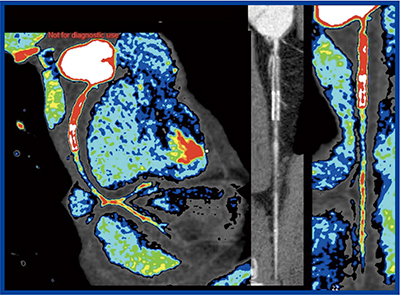

PhyZiodynamicsは,4Dイメージの動態補完が可能であり,画像のノイズ低減や空間分解能の向上はもとより,冠動脈の断面に球形の関心領域(VOI)を設定して自動的にデータを追随することができる(Dynamic VOI)。これにより冠動脈と大動脈の正確なtime density curveが得られるため,maximum upslopeを定量解析に用い,上行大動脈の濃度で補正することでcoronary flow index(CFI)を測定する定量的な評価法を提唱している。

そこで,特に中等度狭窄病変の虚血の診断能について,負荷心筋シンチグラフィをゴールドスタンダードとし,Coronary Flow Imagingの画像から狭窄部位の近位側(proximal)と遠位側(distal)のCFIを測定して虚血の診断能を比較した。対象は冠動脈疾患の36名で,少量造影剤(16〜20mL)を4〜5mL/sで投与し,冠動脈のファーストパスをstep and shoot法で心臓全体を20秒間,R-R75%の拡張位相をねらい撮影を行った。

結果を見ると,正常領域,虚血領域,梗塞領域の比較においてproximal CFIはいずれも0.6前後でほとんど差がなかったが,distal CFIは虚血領域で約0.3と有意に低下していた。CFIのカットオフ値を0.39とすると,虚血の診断能は感度100%,特異度75%であった2)。

Coronary Flow Imagingは,ほかにもさまざまな利用法が考えられる。例えば,ステント留置術後にステント内再狭窄を起こした症例では,coronary flow imageにて側副血行路からの血流を明瞭に描出可能であった(図3)。このため,冠動脈バイパス術後の評価にもcoronary flow imageを利用できると考えている。また,川崎病性冠動脈瘤の症例では,shear stressの低下や血栓による冠動脈瘤遠位側の血流低下がcoronary flow imageで明瞭に描出でき3),これらが川崎病で問題となる心筋梗塞を引き起こす要因の一つと判断できた。

図3 ステント留置術後症例のcoronary flow image

(ステント内再狭窄)

図4 Coronary Flow Imagingの新たな可能性